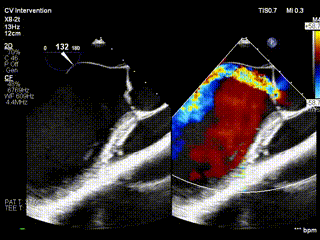

视频1:病例1术前食道超声示重度主动脉瓣反流

视频2:病例1术后心超示主动脉瓣无反流,eH 9.8mm,VBR 23.1mm,窦直径29.6mm,窦管交界 25.4mm。